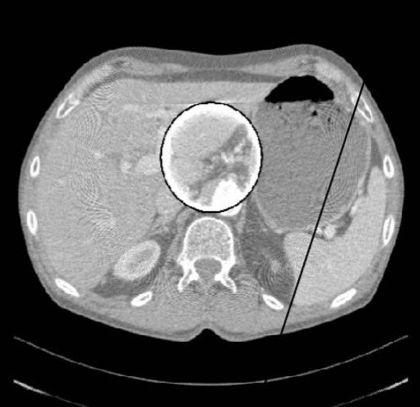

高原子序数或吸收系数大的物体部分投影于扫描平面而产生的伪影称为部分容积效应,也可称为Hounsfield伪影。一般在重建后横向面图像上可见条形,环形或大片干扰的伪影。 部分容积效应可用正确摆放病人的体位,或采用薄层扫描而减弱。

(部分容积效应)